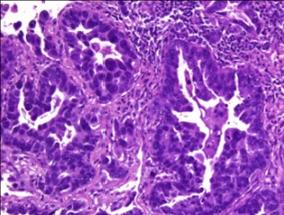

因此,揭示肿瘤特异性指纹甲基化CpG岛的DNA甲基化谱不仅能识别肿瘤类型,还可预测患者预后和抗肿瘤治疗反应。

科学家们使用高通量方法,首次探访了超过1000名患者组织样品的1505个CpG位点,绘制了DNA甲基化图谱,鉴定出24种不同肿瘤类型的特定指纹。在此之前的大多数DNA甲基化模式研究仅局限于少数患者的、屈指可数的特定基因组位点。